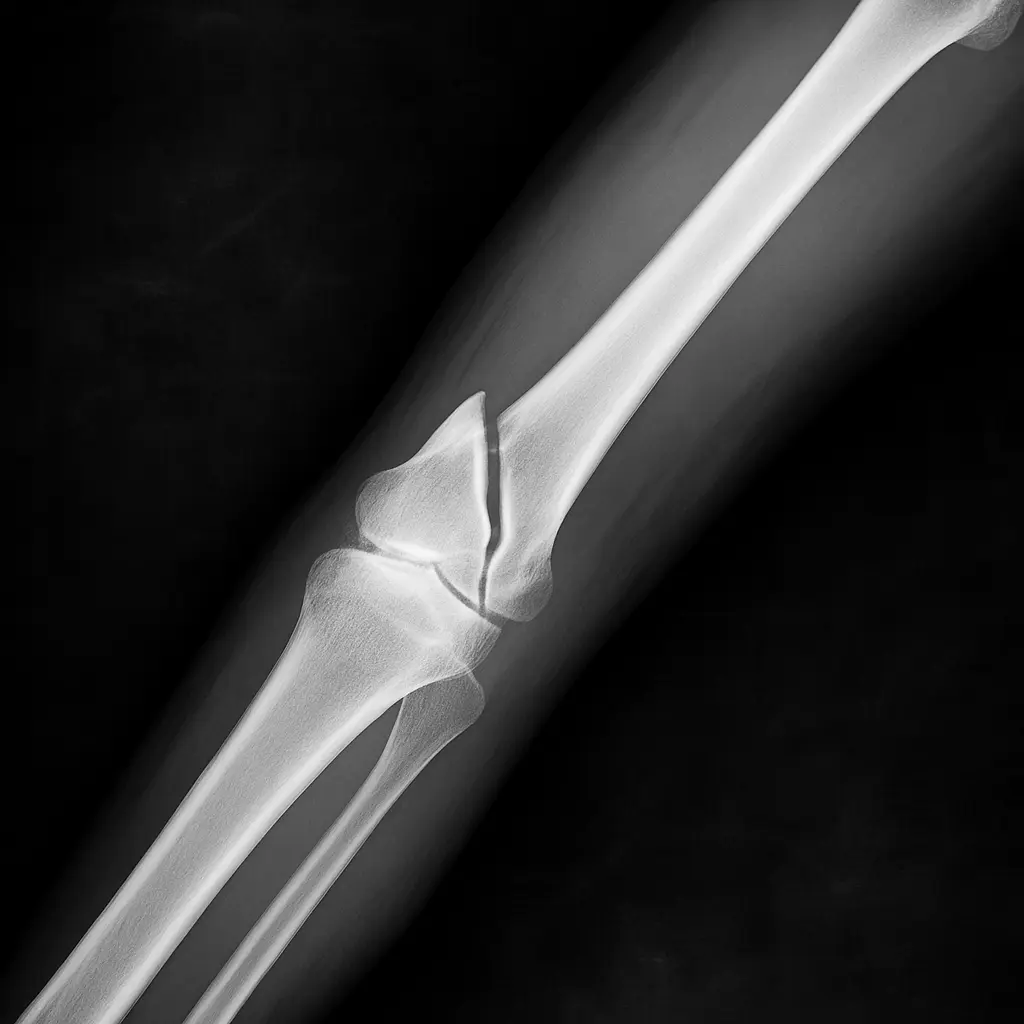

Researchers highlight that “Bone 02” is especially useful for treating complex fractures with small bone fragments that are difficult to secure with conventional methods. In addition, the procedure is minimally invasive, requiring only a small incision to apply the adhesive.

The effectiveness of “Bone 02” has been confirmed through a rigorous prospective, multicenter, randomized, blinded, and parallel-controlled clinical trial involving over 150 patients. The team reported positive outcomes, with complete bonding of all fracture fragments, and plans to publish the detailed findings soon in a specialized medical journal.